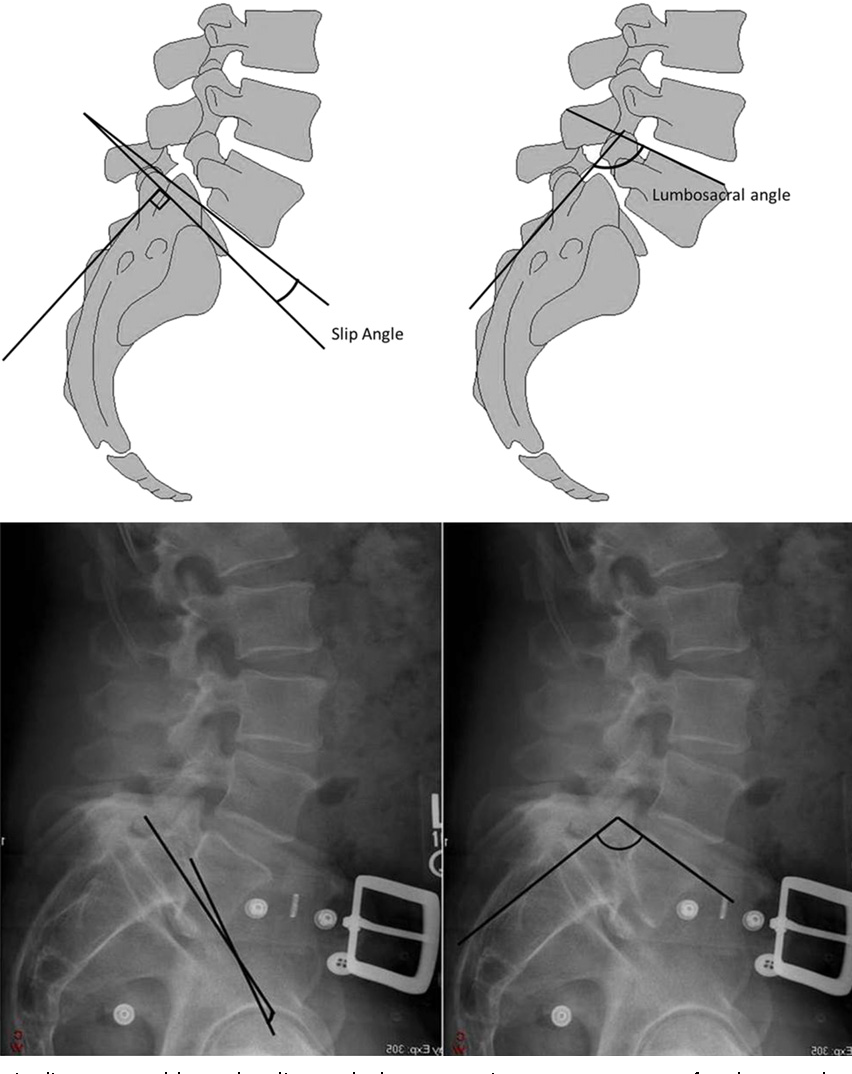

radiologic finding 에서 Slip angle 도 instability나 progression 을 예측하기 좋은 수치입니다.

Slip angle 은 sacrum 후경계부 수직인선과 L5 하종판을 지나는 선의 각도로

Slip angle이 30도 이상인 경우 척추전방전위가 진행될 가능 성이 높으며 55도 이상이면 예후가 좋지 않습니다.

정상은 lordotic 한 것이 정상입니다. (음각)